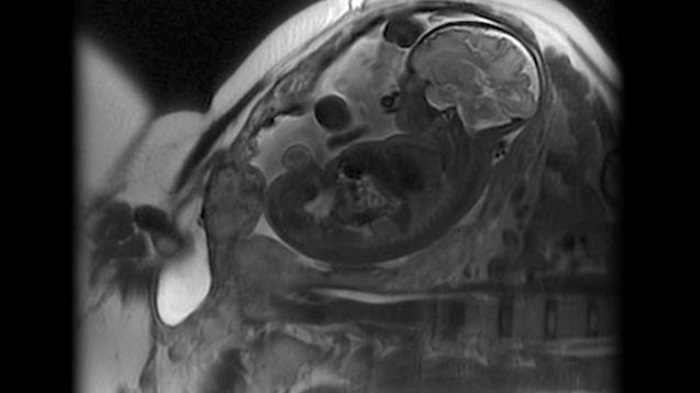

En julio de 2014, la estadounidense Kristen Terlizzi se despertó en la unidad de cuidados intensivos. No pasó mucho tiempo después de que naciera su segundo hijo, Leo. Seis semanas antes, los doctores habían descubierto que la placenta había crecido desproporcionadamente en el útero de la mujer.

Esta es una condición muy rara, que los médicos creen que se debe a cambios estructurales en el útero. Casi siempre se observa en un nuevo nacimiento, especialmente si la primera vez se hizo una cesárea.

La vida de Kristen estaba literalmente colgando de un hilo. Los médicos planearon extirpar la placenta quirúrgicamente después del nacimiento de Leo. Pero, cuando los doctores vieron que literalmente no podían encontrar un lugar que no hubiera sufrido, decidieron coser a la paciente, dejando la matriz en su interior.